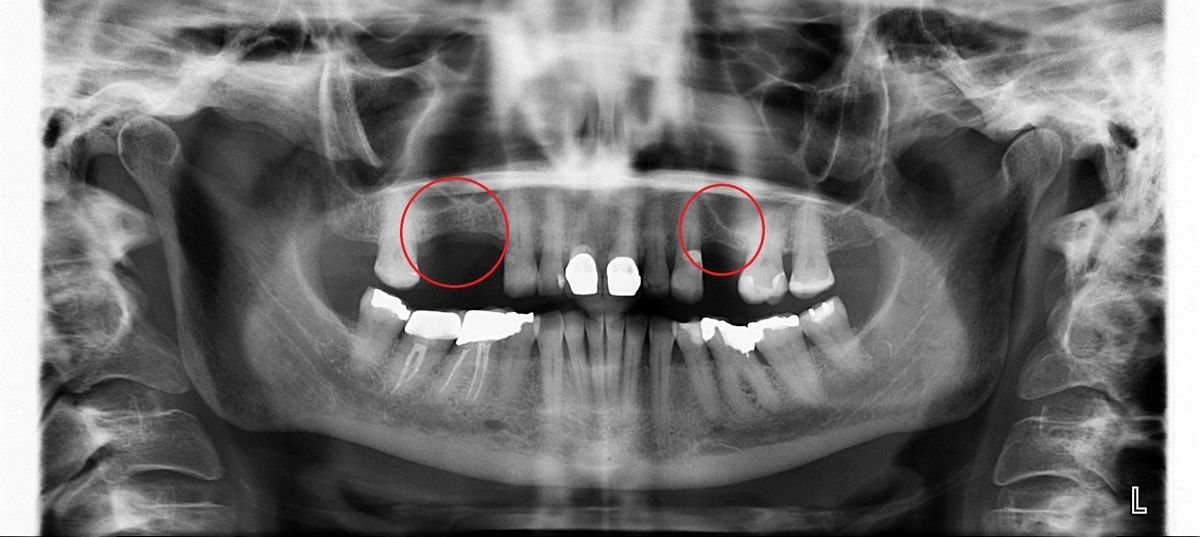

Синус лифтинг

После удаления зуба из-за отсутствия необходимой нагрузки на челюсть, кость в пустующем месте атрофируется. В этом случае перед имплантацией необходимо восполнить объем костной ткани.

Разновидность костной пластики направленной на увеличение объема костной ткани верхней челюсти в районе гайморовых пазух.

Открытый синус лифтинг

Открытый синус-лифтинг применяется, когда для установки имплантата не хватает более 3 мм костной ткани. При проведении этой операции имплантация в ряде случаев возможна только после полного восстановления кости челюсти.

Закрытый синус лифтинг

Закрытый синус-лифтинг подходит для наращивания небольшого объема костной ткани (1-3 мм). Он менее травматичен, чем открытый. Подсадка костного материала проводится через небольшое отверстие для имплантата.

При закрытом типе синус-лифтинга имплантация проводится сразу. Вам не придётся лишний раз посещать стоматолога.

• до синус-лифтинга

• после синус-лифтинга

• после установки имплантатов в верхнюю челюсть

• коронки установленные на имплантаты